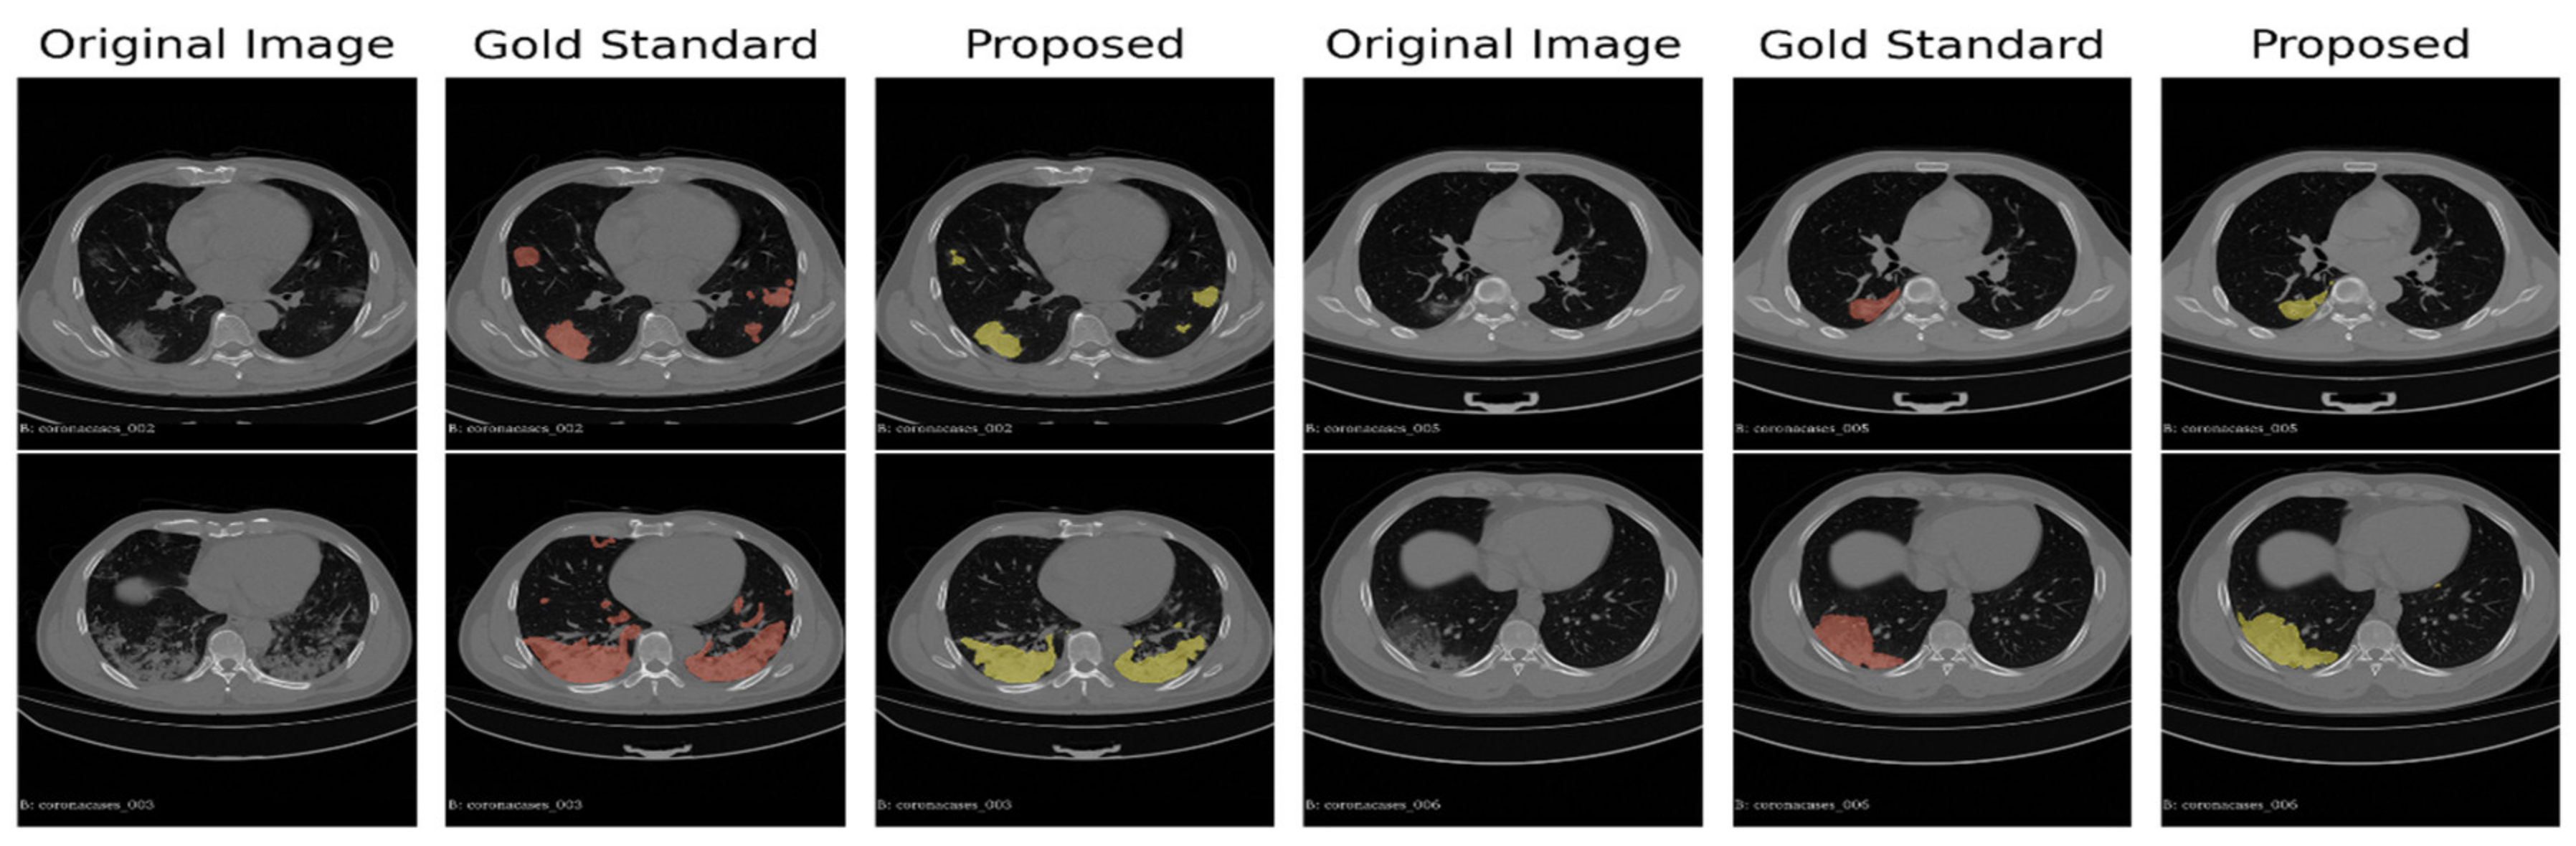

We show in Figure 2 the distribution of the individual scores (Sensitivity, Specificity, Precision, and F1 score). The scores were obtained by the average of the whole 15 scans (overall) on the 10 corona cases (CORONACASES OVERALL) and on the five gold standard (GOLD STD OVERALL). In Figure 3 and Figure 4, we show a visual comparison between the achieved segmentation and the ground truth labels (both for corona cases and the gold standard).

The examples reported in Figure 3 and Figure 4 show how the non-supervised segmentation method proposed in this paper is able to approximate the gold standard results with satisfactory results.

Figure 3. A comparison between the ground truth and the results obtained by the proposed pipeline for the corona cases segmentation. In green are highlighted the GGO areas identified by the experts, and in red, those identified by our segmentation pipeline, respectively.

Figure 4. A comparison between the proposed automated segmentation pipeline and a gold standard segmentation manually performed by an expert radiologist.